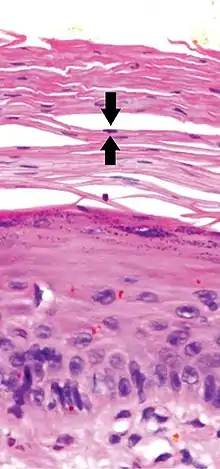

Parakeratosis is a mode of keratinization characterized by the retention of nuclei in the stratum corneum.[1] In mucous membranes, parakeratosis is normal.[2] In the skin, this process leads to the abnormal replacement of annular squames with nucleated cells. Parakeratosis is associated with the thinning or loss of the granular layer and is usually seen in diseases of increased cell turnover, whether inflammatory or neoplastic. Parakeratosis is seen in the plaques of psoriasis and in dandruff.